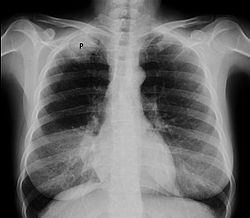

Pankost şişi – ağciyər zirvəsinin şişi olub, yuxarı ətrafın nevroloji və damar simptomları ilə müşayiət olunur.

Pankost şişi